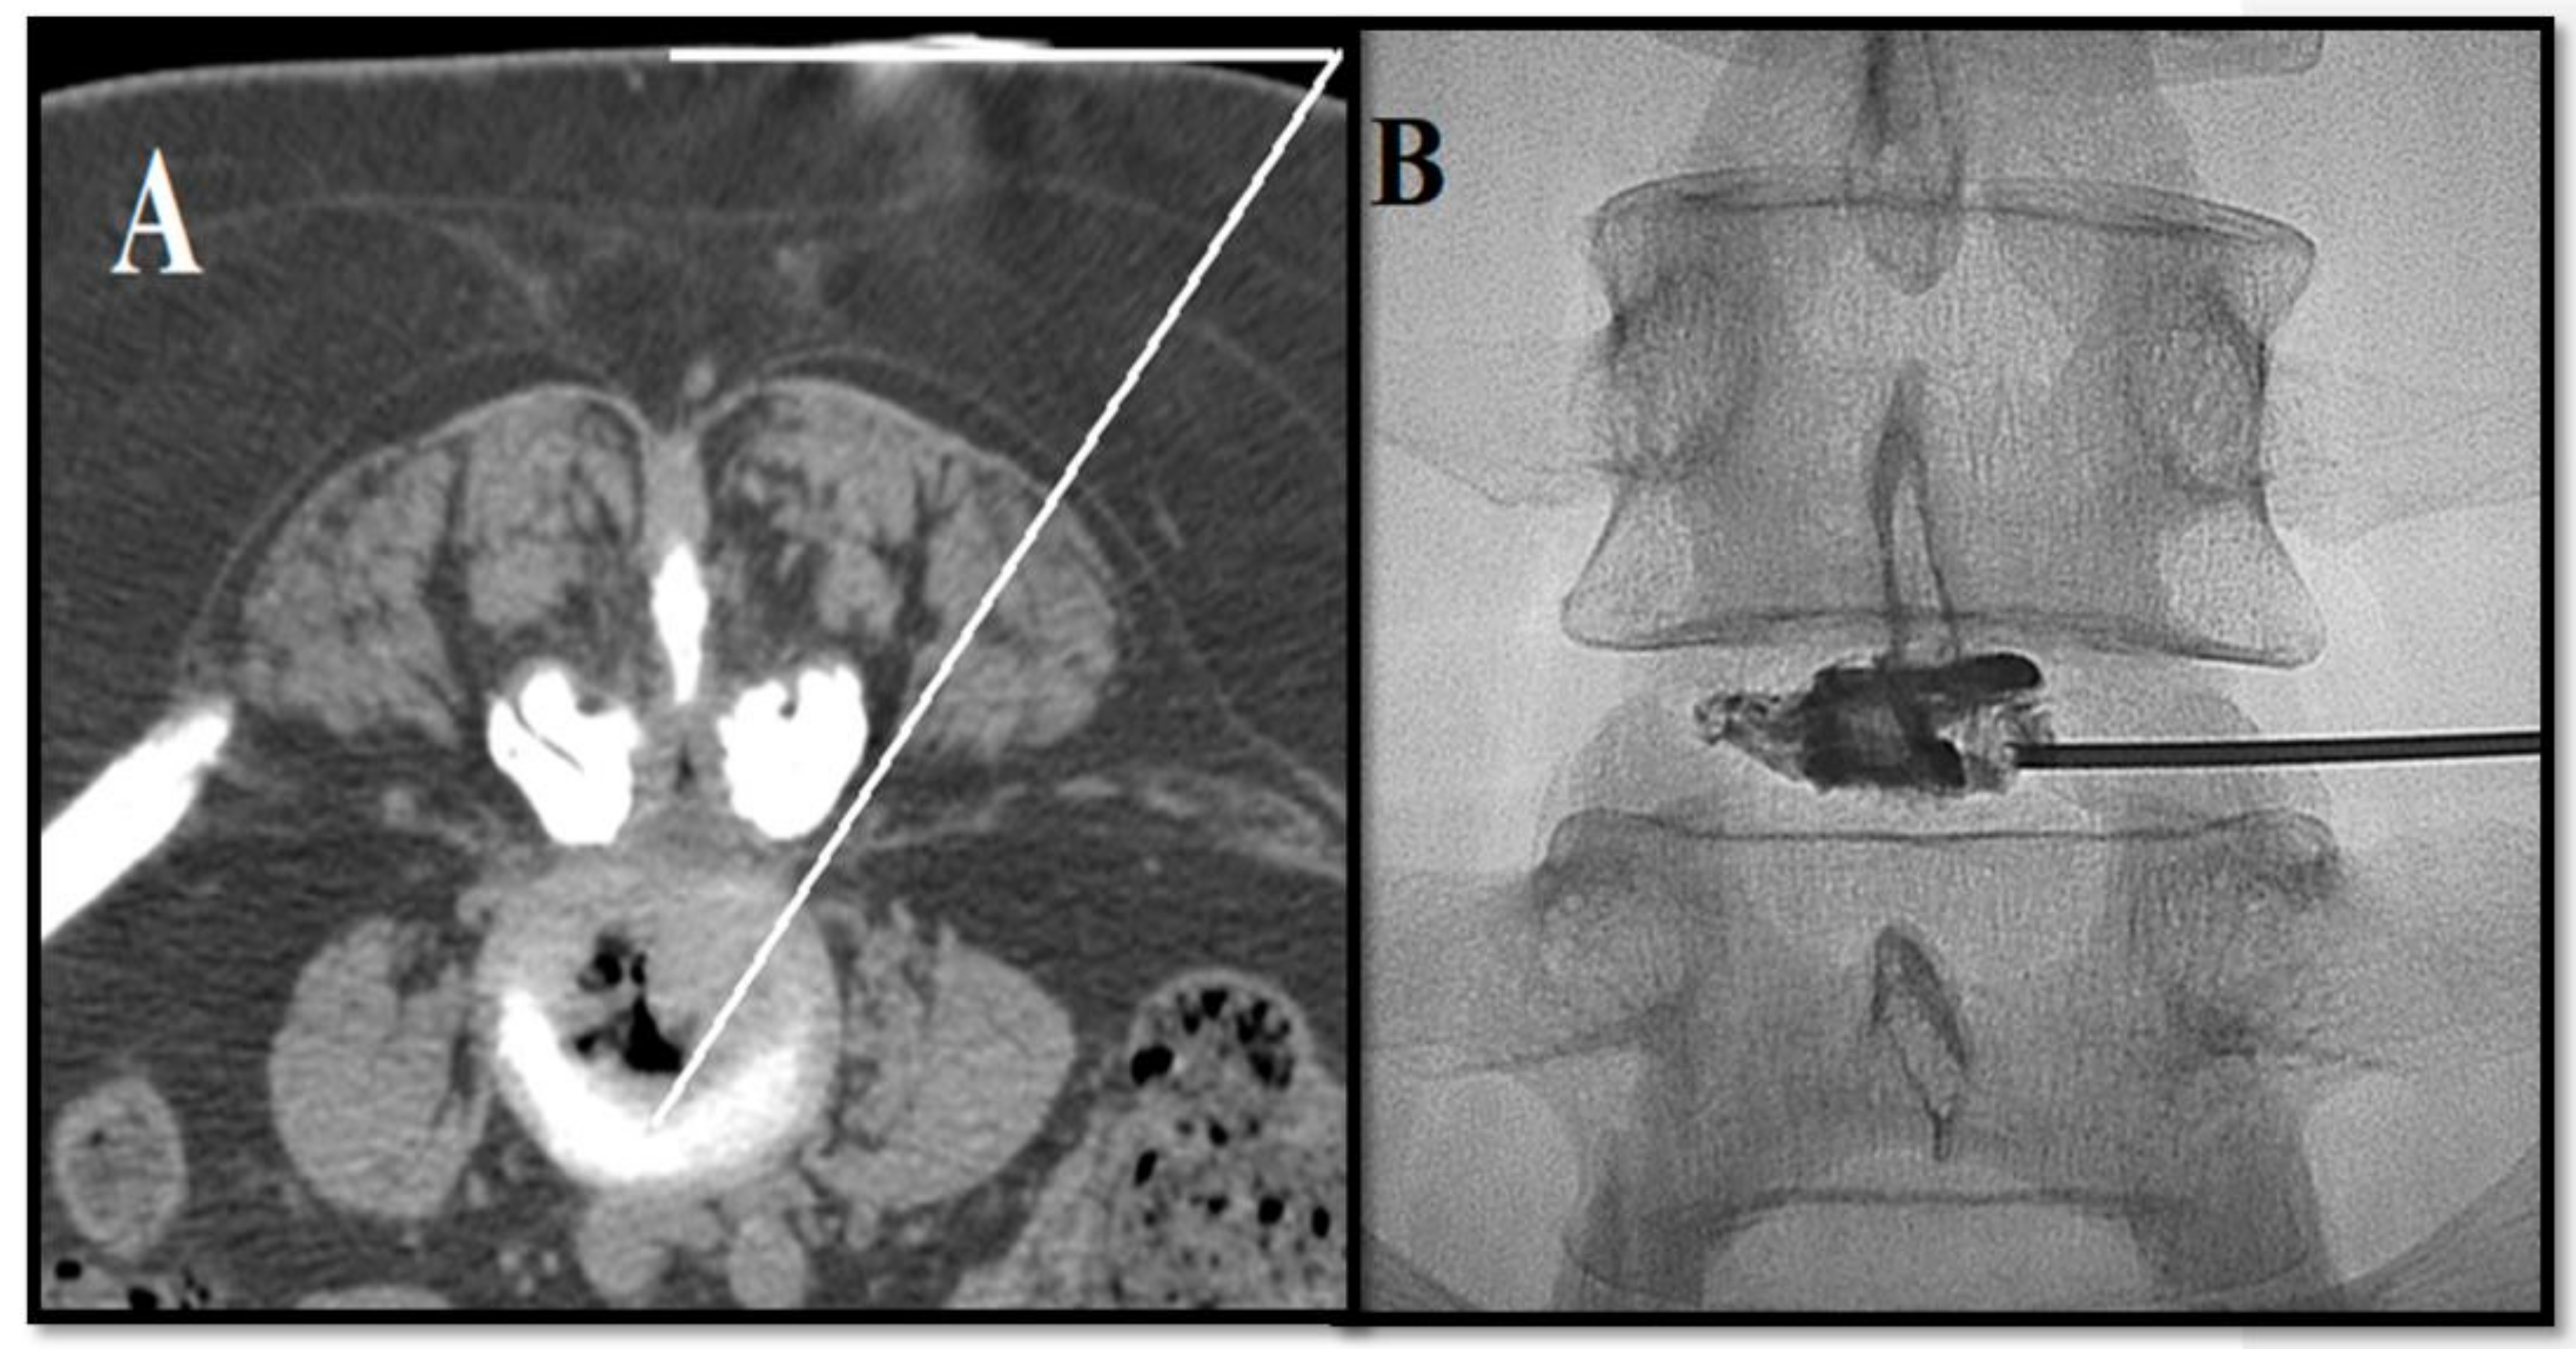

- Kelekis, A.; Filippiadis, D. Percutaneous treatment of cervical and lumbar herniated disc. Eur. J. Radiol. 2015, 84, 771–776. [Google Scholar] [CrossRef]

- Amoretti, N.; Huwart, L.; Marcy, P.Y.; Foti, P.; Hauger, O.; Boileau, P. CT-and fluoroscopy guided percutaneous discectomy for lumbar radiculopathy related to disc herniation: A comparative prospective study comparing lateral to medial herniated discs. Skelet. Radiol. 2013, 42, 49–53. [Google Scholar] [CrossRef]

- Gangi, A.; Tsoumakidou, G.; Buy, X.; Cabral, J.; Garnon, J. Percutaneous techniques for cervical pain of discal origin. Semin. Musculoskelet. Radiol. 2011, 15, 172–180. [Google Scholar] [CrossRef]